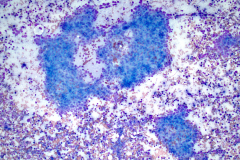

BSCC reportedly display very high nuclear/cytoplasmic ratio with coarse chromatin, inconspicuous to prominent nucleoli and nuclear pleomorphism. The nuclei also mold, and the cells tend to arrange in cohesive clusters, with necrosis in the background.6 This case demonstrates all these criteria (see figures 1-4).